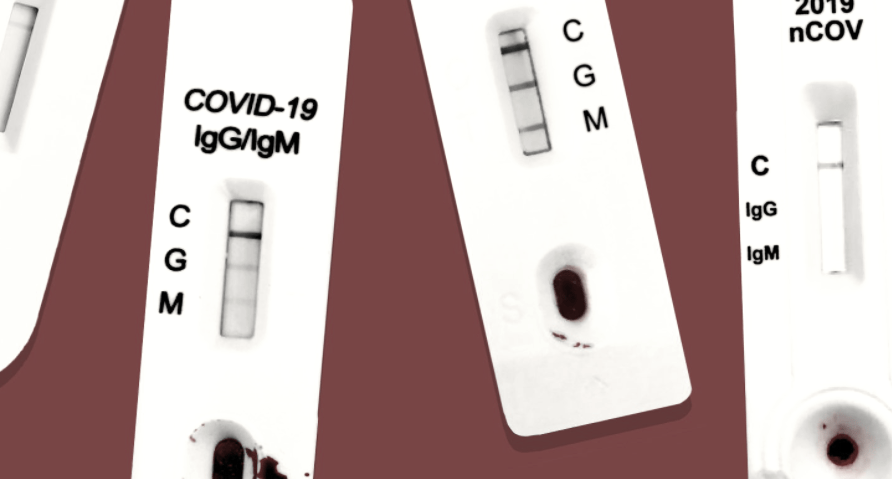

(Bild Off-Guardian)